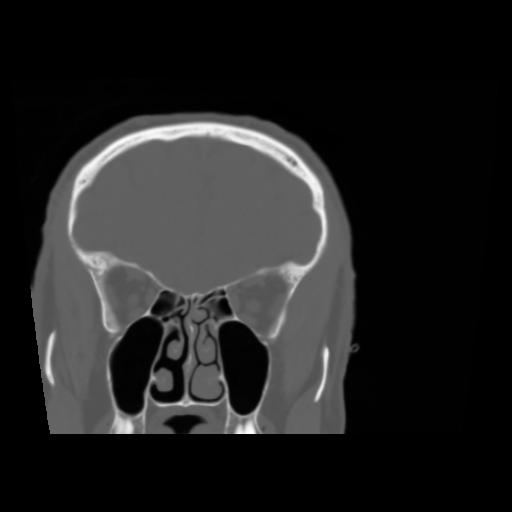

5 CEREBRO,,Coronal,3.000,CEREBRO,Coronal,